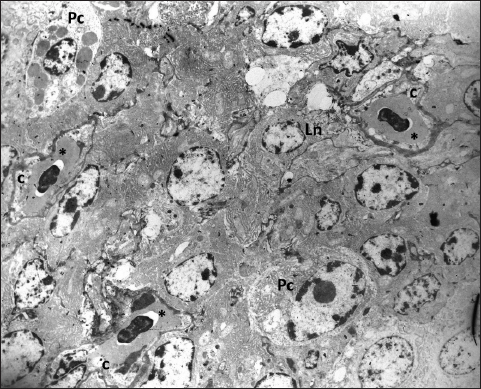

Ultrastructural analysis shows that the tissue of the Harderian gland has capillaries with a thin endothelium and occasionally visible fenestrae (Fig. 5). The fenestrated capillaries are identified in the subepithelial region, as well as in the deeper part of the glandular tissue, where they come into close contact with lymphocytes and plasma cells (Figs. 6 and 7).

Following the course of venous blood vessels, unlike Wight et al. (1971), we identified three veins that drain the gland. Two of them drain the main part of the gland and both inflows separately into the v. ophthalmoteporalis, while the third, enters into the v. nasalis communis. As for arteries, we did not find any data in the present literature regarding the drainage of the gland by the branches of the common nasal vein. In a recently conducted study of cephalic vascularization in turkey and turkey vulture birds, the main intraorbital blood vessels are shown in figures, but the arteries and veins that supply the Harderian gland are not labeled or described in the manuscript (Arad et al., 1989; Porter and Witmer, 2016). Comparing the vascular pattern of this research with our findings we can say that the vascularisation of the gland is very similar between these bird species. Also, comparing the methodology of the research, we can say that both, the corrosive cast technique and CT scanning with the use of contrast media can be equally useful for the display and general study of the distribution of blood vessels, with the fact that CT scanning is practically more convenient and easier to perform. On the other side for fine, ultrastructural research of blood vessels, the use of TEM is still irreplaceable. Ultrastructural research of the Harderian gland conducted on small mammals (common tree shrew and hamster) shows that the gland possesses two capillary types, small fenestrated and irregular sinusoidal (Pradidarcheep et al., 2003; Menendez-Pelaez et al., 2012). Our research by TEM shows that the gland in hens possesses only fenestrated capillaries and this confirms the previous findings of Wight et al. (1971).

Fig. 6. The fenestrated capillaries (c) containing erythrocytes are present in the stroma of the gland where they are surrounded by lymphocytes (Ln) and mature plasma cells (Pc); TEM, 3000X.